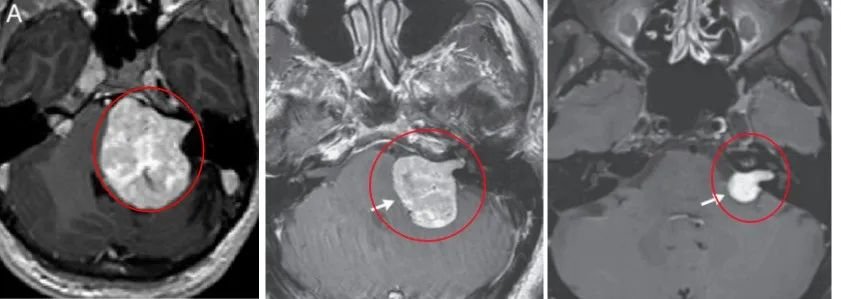

娜娜的听神经瘤巨大,典型的“冰淇淋”征象,“冰淇淋尾”是听瘤粘附着骨质内听道里面听神经的所在之处,也是肿瘤难以全切、易导致面瘫和听力下降的关键。

在这场与肿瘤的博弈中,INC国际教授用精湛的技艺完成了高难手术:不仅将这颗危险的“冰淇淋”成功切除,更保住了娜娜最珍贵的灿烂笑容。

术后7年MRI

听神经瘤可引起内听道扩大, 突向小脑桥脑角部, 充填于小脑桥脑角内, 呈特征性的“冰激凌圆锥”征。甜筒冰激凌征为头颅MRI上,桥小脑角池占位的一端呈锥形、伸入同侧扩大的内听道内,一端膨大,位于桥小脑角池内,肿瘤形似甜筒冰淇淋。

典型听神经瘤MRI影像呈冰淇淋甜筒征